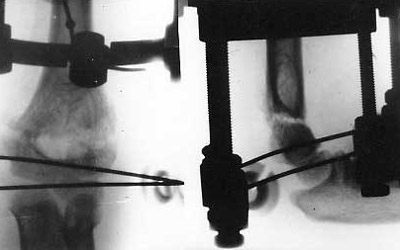

Osteosynthesis of upper arm by means of Veklich's apparatus. Osteosynthesis of upper arm by means of Veklich's apparatus.

Osteosynthesis of upper arm by means of Veklich's apparatus.

Results of treatment.